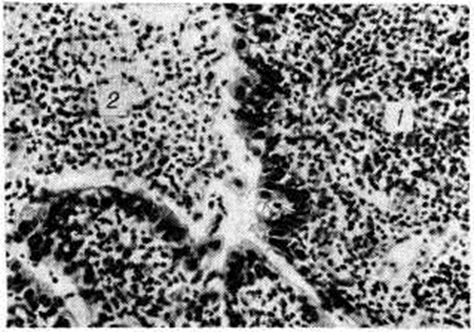

Рис. 2.

Микропрепарат осадка мочи больного острой гонореей: видны группы гонококков в лейкоцитах и вне их; окраска по Граму.